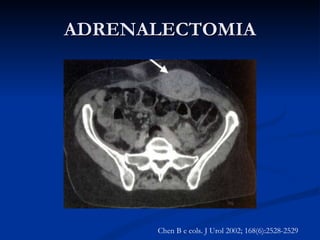

ADRENALECTOMIA Metástase de pequenas células de carcinoma de pulmão Chen B e cols. J Urol 2002; 168(6):2528-2529

ADRENALECTOMIA Metástase depequenas células de carcinoma de pulmão Chen B e cols. J Urol 2002; 168(6):2528-2529